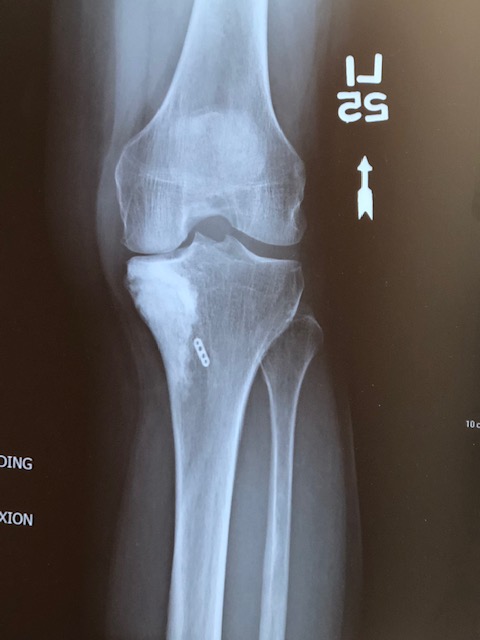

Ouch!